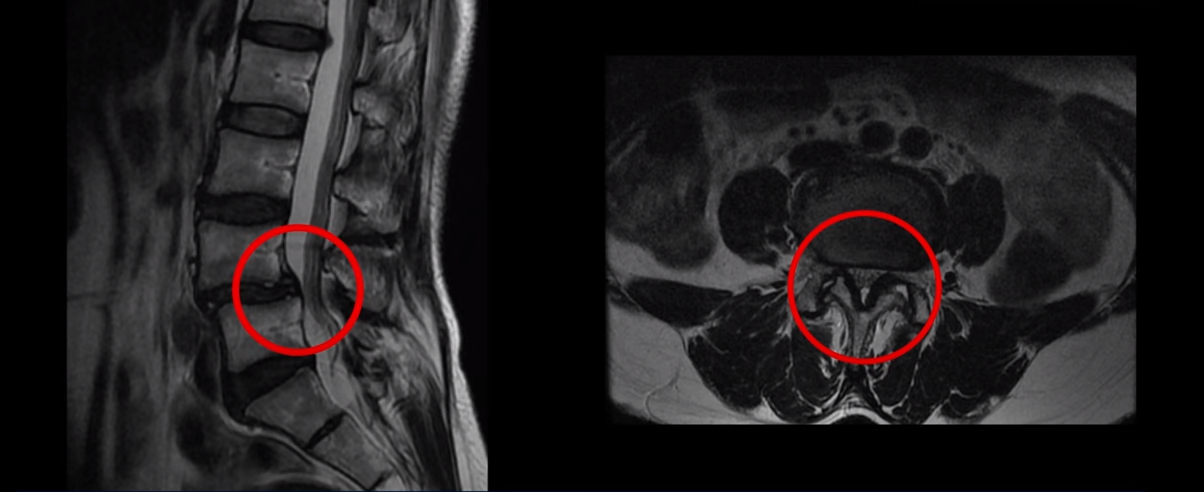

이 환자분은 MRI에서 보시다시피 4번 5번에 전방전위증이 있습니다. 전방전위증이 있는 분들은 디스크 문제나 협착증 문제를 동반하는 경우가 많은데 이분은 4,5번 디스크에 큰 문제는 없으시고 척추관이 약간 좁아져 있으나 다리 쪽의 증상은 전혀 없고, 오로지 만성허리통증만 있습니다. 3년 동안 허리가 심하게 아프신 상태입니다. 참고로 이분은 심하게 넘어지면서 엉덩이 근육 파열로 입원하신 상태에서 만성 허리통증 치료를 함께 받으셨습니다. 그런데 저희가 만성 허리통증이 있는데 ‘허리에 디스크가 보이든, 협착증이 보이든, 전방전위증이 보이든, 만약 다른 증상 없이 허리 통증만 있다면 그건 근육의 문제일 가능성이 매우 높다’고 여러 영상에서 설명 드렸습니다. 이분을 처음 진찰했을 때 허리 주변 근육들과 엉치 근육을 꼼꼼히 만져보았는데 역시 허리통증과 연관되어있는 중요한 근육들, 장요근, 요방형근, 기립근, 둔근이 모두 다 심하게 굳고 뭉쳐있었습니다.

허리에 디스크, 협착, 전방전위 등 무엇이 보이든 다른 증상 없이 허리만 아프다면 이건 결국 근육문제 입니다. 즉, 뼈가 밀려 나가있어도, 디스크가 있어도, 협착이 있어도 근육 상태가 아프지 않고 좋으면 안 아플 확률이 매우 높습니다. 그래서 근육 재활치료가 중요한 겁니다.